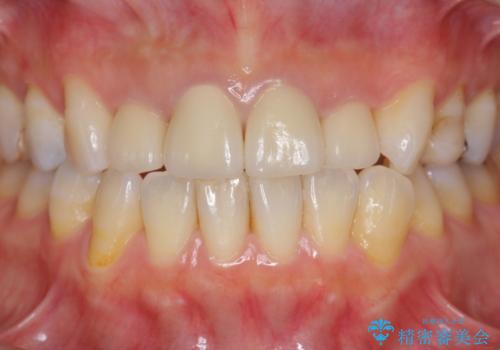

自然で美しい前歯の仕上がりとなり、大変満足していただくことができました。

- 52.8万円(ジルコニアクラウン×4・仮歯×4)費用は治療当時の料金となります